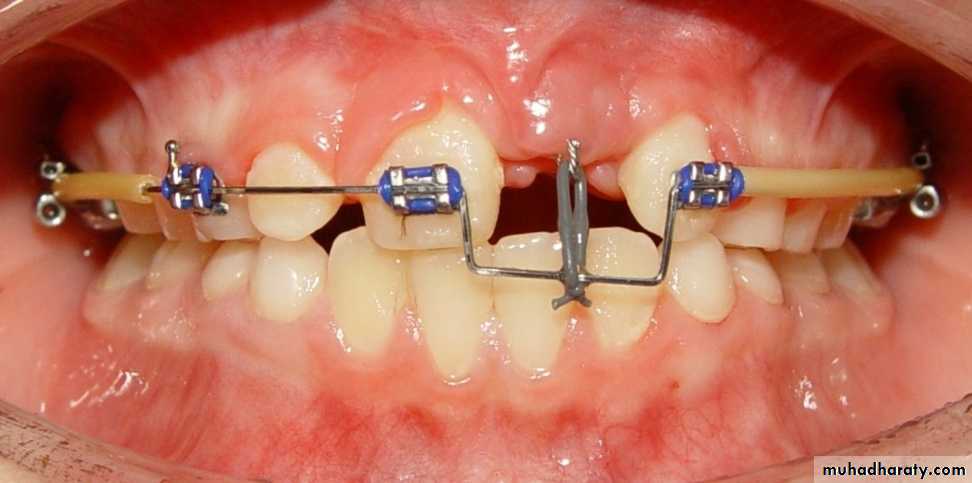

4- Premature loss of deciduous teeth

The early loss of primary teeth should be considered as a “Malocclusion Maker”Deciduous teeth not only serve as organs of mastication, but as spacesavers for permanent teeth. Loss of a deciduous 2nd molar will lead to mesial driftof the 1st permanent molar and blocking of

erupting 2nd premolars.In this cases appropriate

space maintainers should be given.